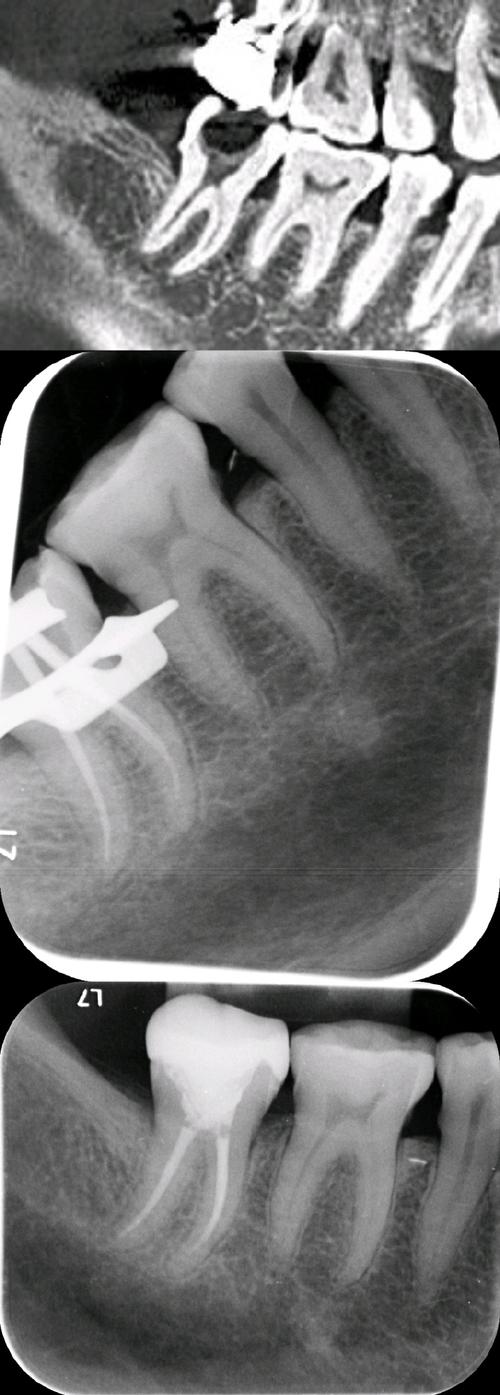

| X线片检查 | 可见根尖周骨质破坏暗影;若存在正畸龋,可见牙体组织低密度影 | 排除根尖周炎,判断牙髓炎症是否扩散;评估正畸装置对牙根及牙槽骨的影响 |

正畸前需进行详细的口腔检查,包括牙髓活力测试(冷热测试、电活力测试)、X线片(曲面断层、根尖片)评估牙根形态、根尖周情况及牙槽骨密度,对存在深龋、牙隐裂、牙髓钙化或根尖周病变的患牙,需先完成根管治疗或充填治疗,再开始正畸,对于糖尿病患者、老年人等高危人群,需控制全身病情,降低牙髓炎症风险。

遵循“轻力矫治”原则,避免使用过大的矫治力(如关闭间隙时采用“滑动法”而非“关闭曲法”,减小每一步的移动量),牙齿移动速度控制在0.5-1mm/月,定期拍摄X线片监测牙根位置及根尖周骨质情况,发现牙根吸收或骨质破坏时,及时调整矫治力,对于需要植入支抗钉的患者,术前需精准定位,避开牙根根尖部,减少对牙髓的机械刺激。

正畸治疗中,定期(每6-12个月)进行牙髓活力测试及X线片检查,对比牙髓活力变化及根尖周情况,患者若出现自发性疼痛、冷热刺激痛等症状,需立即复诊,早期诊断、早期治疗,避免炎症扩散导致牙髓坏死或根尖周炎。

A:通常可以,根管治疗后,患牙失去牙髓的营养供应,牙体组织脆性增加,但只要根管充填完善,无根尖周炎症,且牙根无严重吸收,仍可继续正畸治疗,不过需注意:①治疗后需观察3-6个月,确认根尖周病变稳定(X线片显示根尖暗影缩小或消失)后再恢复矫治;②正畸中需减小矫治力,避免使用过大力量导致牙根吸收或牙体折裂;③对于大面积缺损的患牙,根管治疗后需行桩核冠修复,增强牙体强度,防止治疗中牙折,若根管治疗后出现牙根严重吸收或根尖周病变持续加重,需与正畸医生共同评估,必要时调整治疗方案或终止正畸。